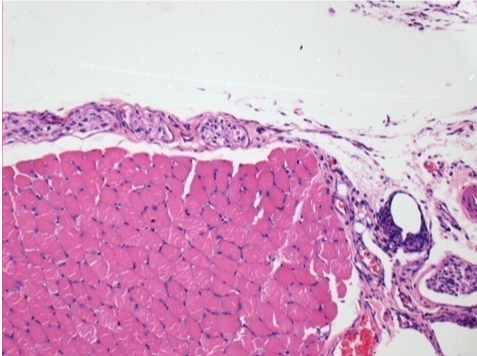

L:Pretibial-No treatment

10 days after Endopeel Injection 0.1ml in the right pretibial muscle.

Here you may see the formation of the vacuoles which are surrounded by lymphocytes. Vacuoles are different from tissue necrosis . The presence of lymphocytes is related to the permeability of the cell membranes.